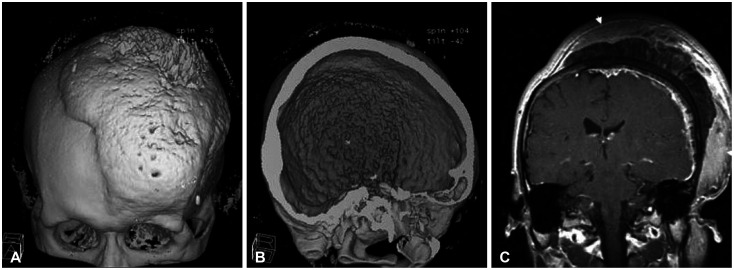

The authors report an extremely rare case of a massive hyperostotic meningioma en plaque, which had characteristics of unique bony growth. A 34-year-old man presented with a palpable solid mass in the left cranial region that had gradually grown in size with a broad base on the calvarium for 8 years. Radiologically, the area involved by the mass ranged from the sphenoid bone to the frontal, parietal, temporal, and occipital bones. Three-dimensional CT revealed multiple growing spiculate features on the inner and outer cranial surface. Even though the radiologic features resembled fibrous dysplasia, it was histologically found to be a type of meningioma.